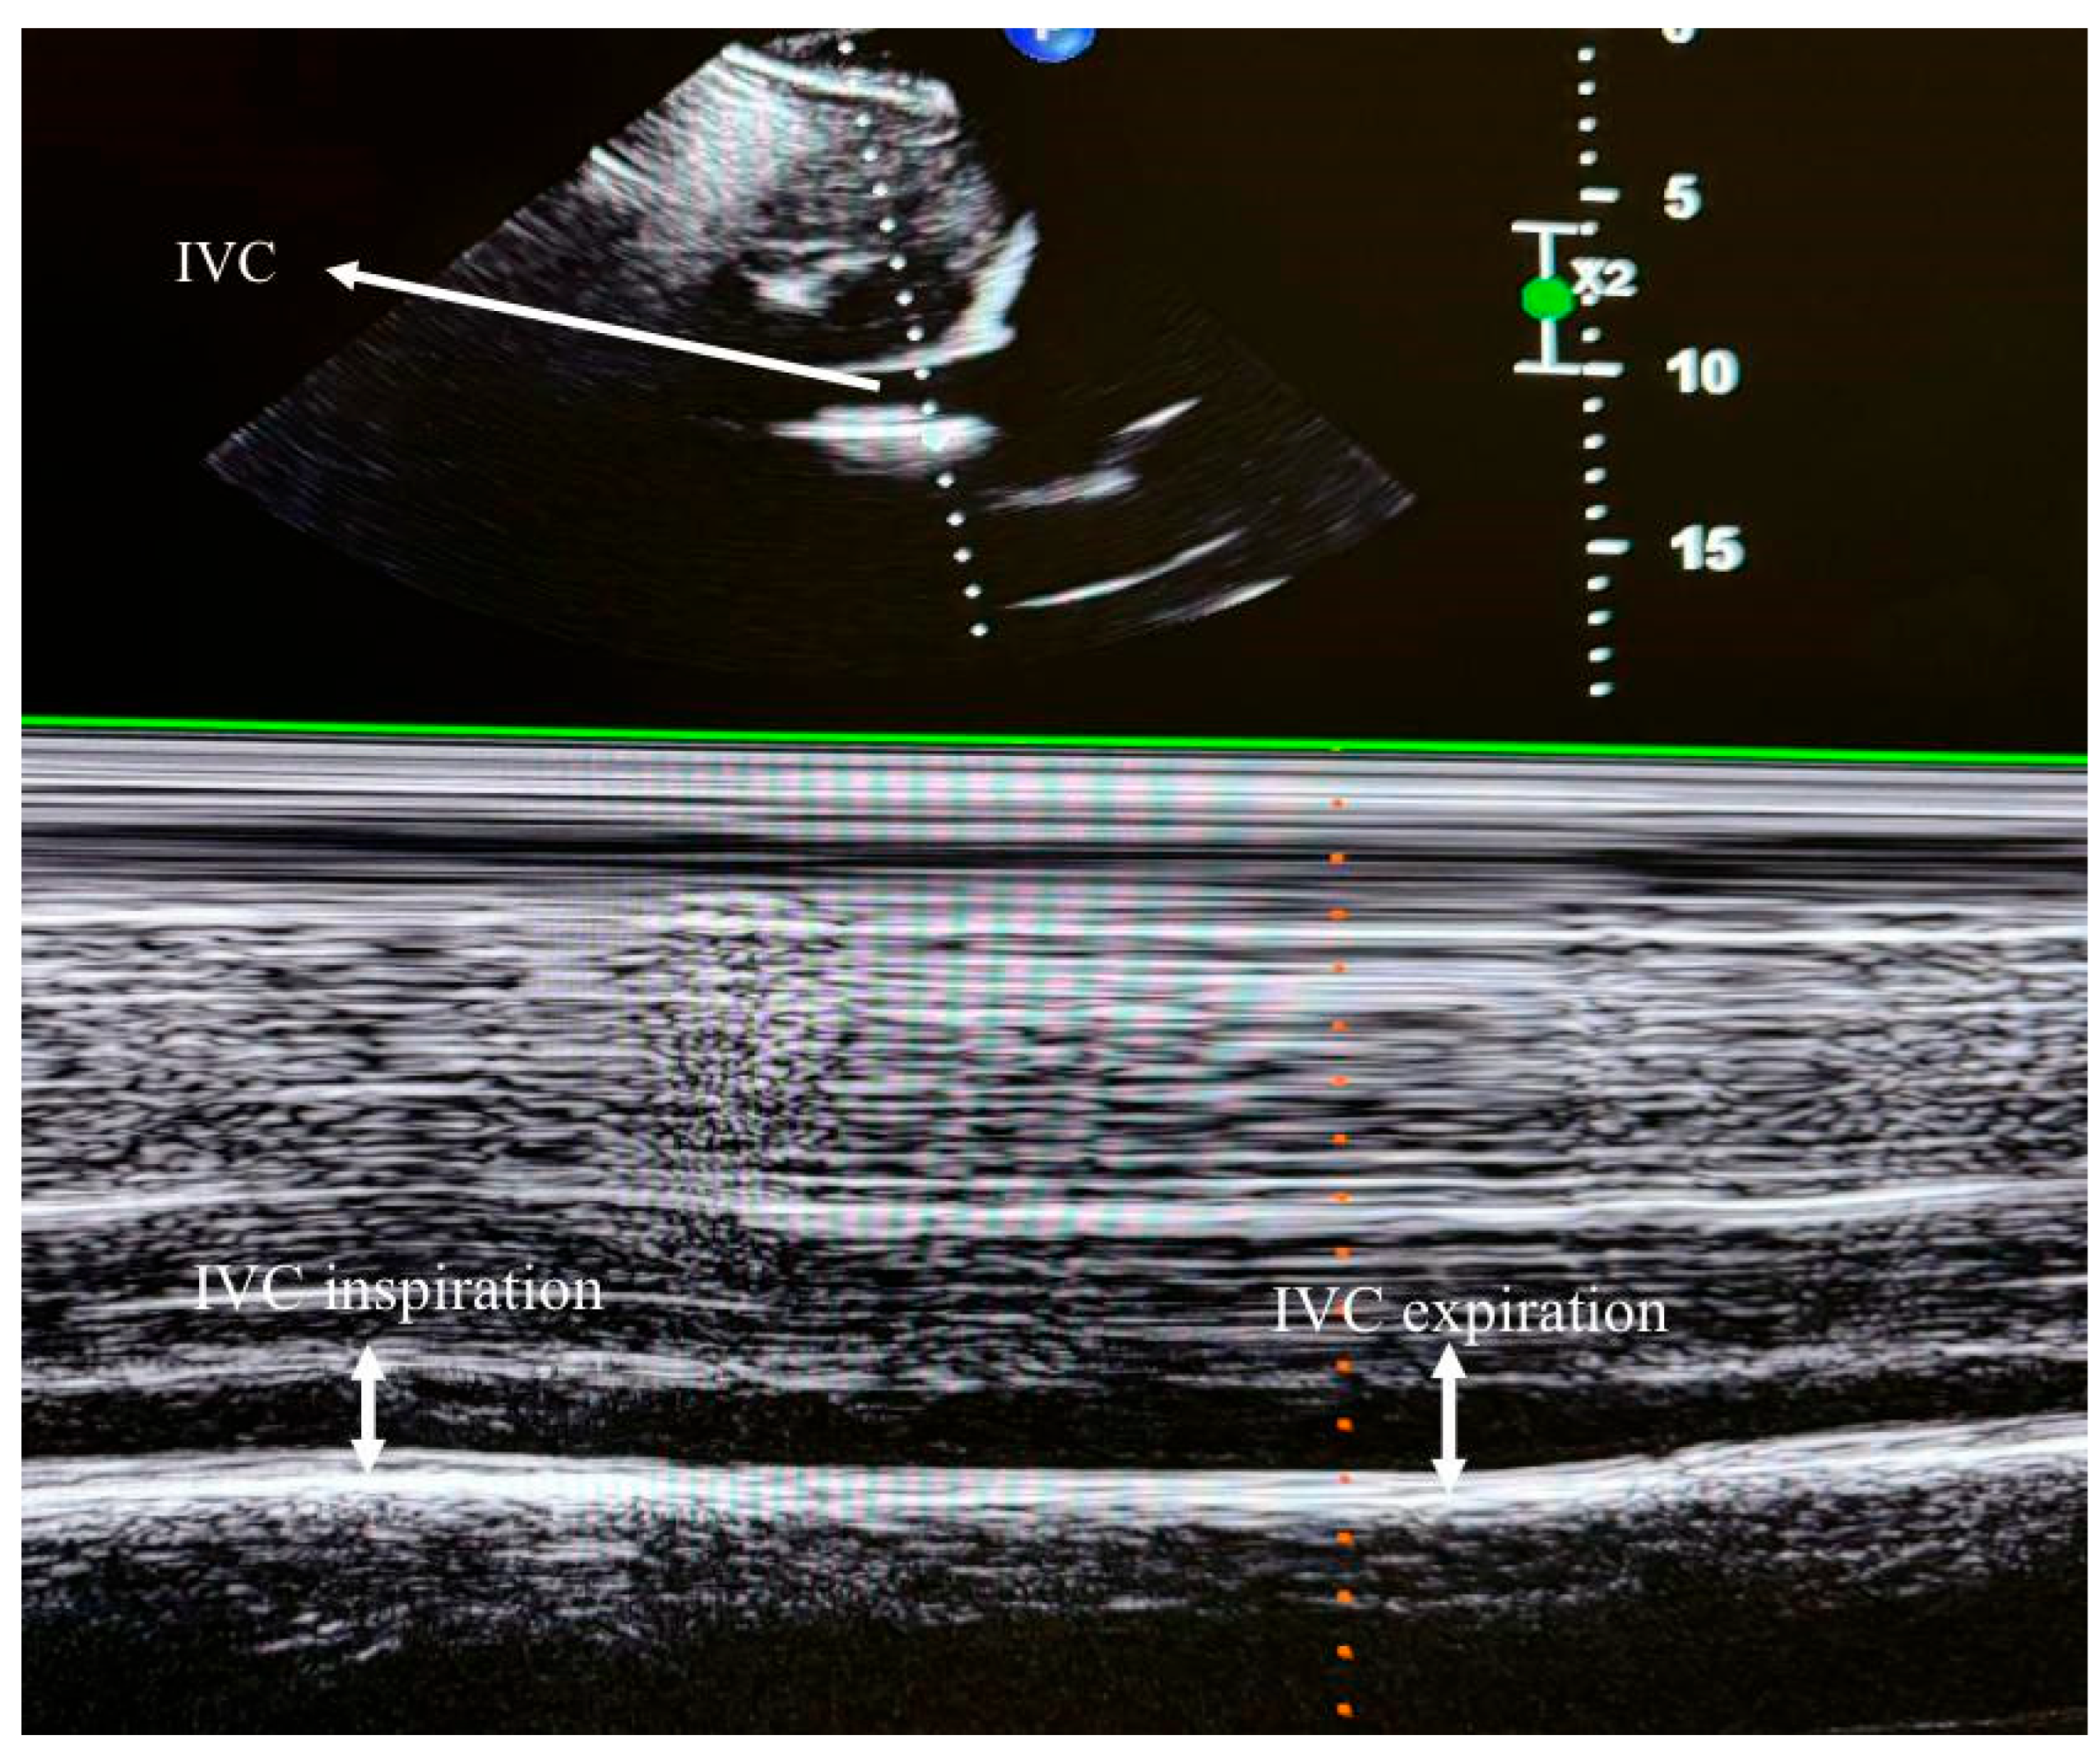

2.3. Transthoracic Echocardiography (TTE) and Data Collection

| IVC inspirium | 10.47 ± 3.62 | 9.73 ± 4.32 | 0.412 |

| IVC expirium | 15.39 ± 3.85 | 15.46 ± 4.37 | 0.941 |

| IVC-CI | 0.37 (0.22–0.45) | 0.38 (0.29–0.51) | 0.305 |

- No significant differences were observed in IVC-CI values between patients with and without hypotension.